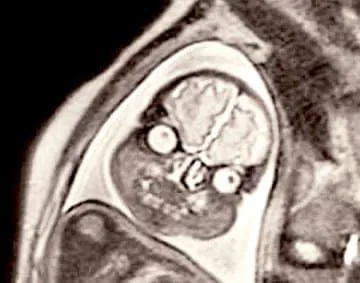

놀람주의) 임산부에게 MRI가 아니라 초음파 촬영을 권하는 이유

정밀한 진단이 필요한 상황이 아니라면 굳이 놀래킬 이유가 없기 때문